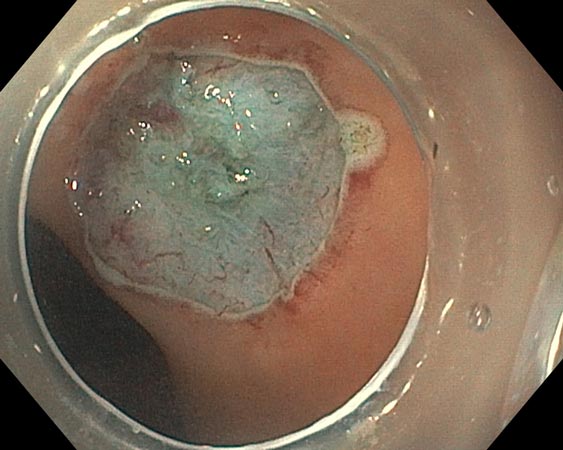

Проводили удаление образования единым блоком для проведения патоморфологического исследования. В случае моноблочной и фрагментарной резекции образования использовали диатермическую петлю SD-210U-25. Сведение краёв клипсами выполняли только после диссекции подслизистых образований (рис. 3–6).

Рис. 3. Частично окаймляющий разрез

Рис. 4. Диссекция в подслизистом слое

Рис. 5. Дефект после удаления

Рис. 6. Клипирование дефекта